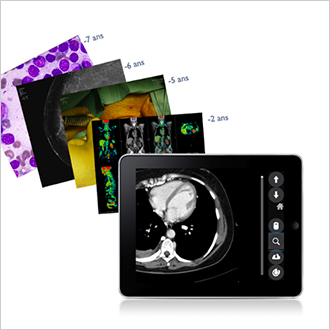

TM-MACS

Il MACS (Multimedia Archiving and Communication System) è in linea con la tendenza alla digitalizzazione dei servizi e delle attività cliniche. La soluzione multimediale si estende a tutti gli altri reparti clinici (oculistica, dermatologia, cardiologia, sala operatoria, pronto soccorso, patologia ecc.). Telemis supporta tutti i formati di immagine, sia DICOM che non DICOM. Il personale medico ha accesso alle immagini e ai video delle cartelle cliniche dei pazienti e può così esaminarle e formulare diagnosi. A tale scopo, sono disponibili diversi strumenti di analisi e di visualizzazione, tra cui zoom, lente di ingrandimento, annotazioni, misurazione delle distanze ecc., per migliorare i risultati diagnostici. L'applicazione di etichette consente di formare gruppi di esami e di accedervi tramite un semplice clic. Un sistema di ricerca personalizzato recupera rapidamente la cartella del paziente o l'esame desiderato.